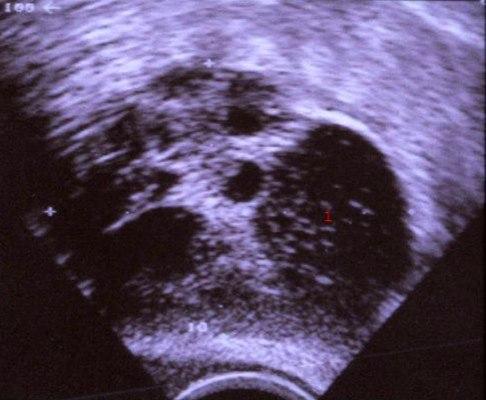

Dermoid cyste

1. Dermoid cyste